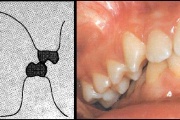

Koonilise kujuga lisahammas ülemiste tsentraalsete lõikehammaste vahel.

Suulaepoolt lõikunud koonilise kujuga lisahammas